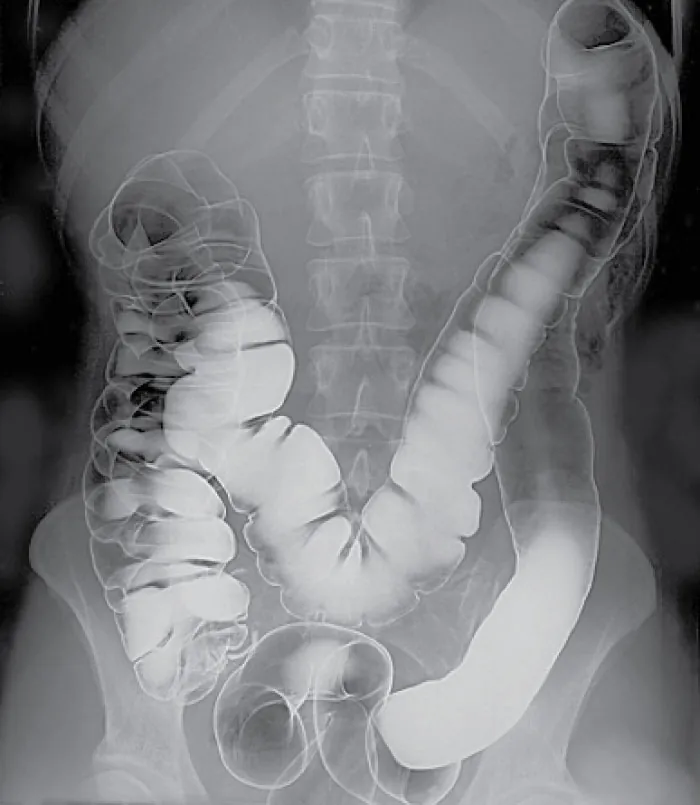

A special dye, called contrast, is administered to patients before some tests so that certain areas show up better on the x-rays, MRIs, and CT scans (Figure 27.5). If contrast is used, the patient may be required to remain NPO (nothing passed orally/by mouth) for four to six hours before the test. Contrast can be administered orally or intravenously (IV). Oral contrast has a chalky taste and will pass out of the body through the stools. Patients receiving IV contrast may feel a slight burning sensation, metallic taste in the mouth, or warm flushing of the body that resolves in a few seconds.

Image of colon in x-ray coated with barium.

Figure 27.5 During a barium enema, the barium coats the lining of the colon, making it visible on the x-ray images. This allows the radiologist to evaluate the size, shape, and contour of the colon, as well as the presence of any abnormalities, such as polyps, tumors, or areas of inflammation. (credit: “Human intestinal tract, as imaged via double-contrast barium enema” by “Glitzy queen00”/Wikimedia Commons, Public Domain)

Before sending the patient for a procedure using contrast, check for previous allergies to iodine or other contrast dyes. Some patients may be prescribed diphenhydramine or corticosteroids before receiving the contrast if they have had a previous allergic reaction. Verify the patient’s kidney status because IV contrast can worsen kidney function. If the patient is currently taking the antidiabetic medication metformin, there may be restrictions placed on the administration of metformin before or after the procedure. This is because the contrast dye used in these imaging tests can affect kidney function, and metformin can accumulate in the body if the kidneys are not working properly, potentially leading to a serious condition called lactic acidosis. For example, patients may be advised to stop taking metformin forty-eight hours before the procedure and to refrain from resuming it until forty-eight hours after the procedure, pending the confirmation of normal kidney function. Jewelry should be removed before the procedure. After the procedure, encourage patients who have received contrast to increase their fluid intake to help eliminate it from their body, as appropriate (Medline Plus, 2022).

After undergoing a barium enema study, patients may experience a sense of relief after the enema is complete, and they can typically resume their normal activities shortly afterward. In the hours following the procedure, patients will likely pass the barium contrast material during bowel movements, resulting in stools that are white or light-colored because of the presence of the contrast material. This is a normal part of the process, and it is essential for the patient to stay hydrated to help flush the barium out of the system. Some patients may experience mild abdominal discomfort or cramping after the procedure, which should resolve within a few hours. Changes in stool consistency, such as firmer stools, may occur temporarily because of the presence of the contrast material; however, increasing fiber intake and staying hydrated can help normalize stool consistency. While rare, severe side effects such as allergic reactions to the contrast material or bowel complications may occur, requiring immediate medical attention if experienced.